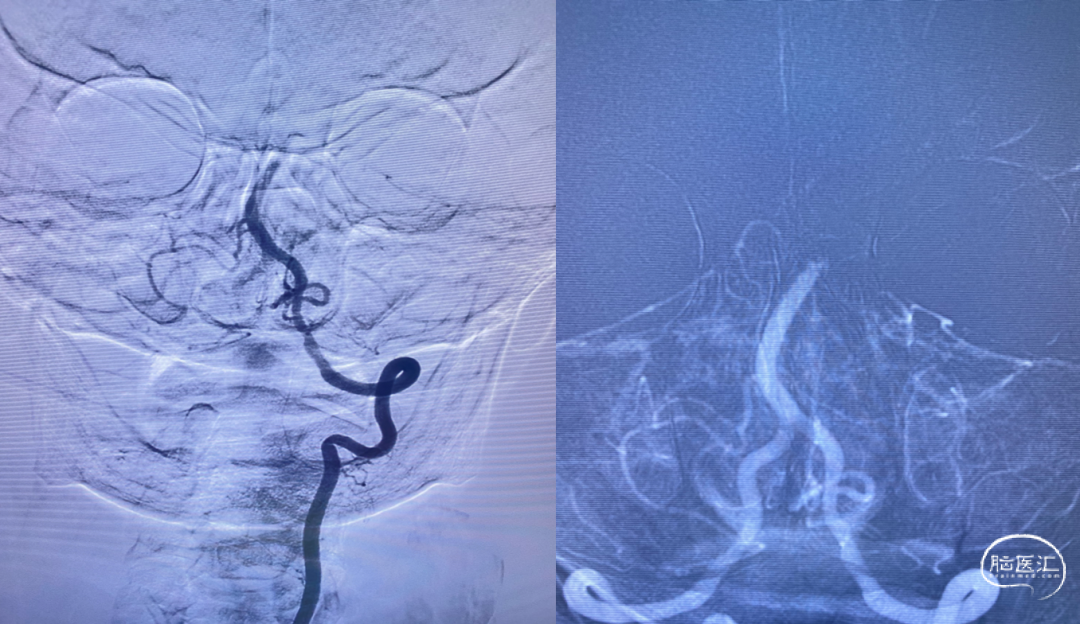

CTA提示:基底动脉闭塞。

脑血管造影提示:左侧颈内动脉起始段重度狭窄,基底动脉尖闭塞,栓塞可能性大

持续保持负压约2分钟后,持续负压抽吸下缓慢撤出抽吸导管,撤出抽吸导管过程中出现回血通畅。手推造影,见基底动脉显影良好,双侧大脑后动脉显影良好,双侧小脑上动脉显影良好,TICI 分级3级。